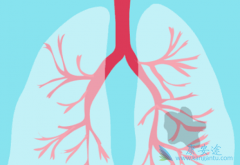

患者出现肺癌咳血症状时应立即就医

患上肺癌之后,患者的身心都会受到一定程度的折磨,出现许多让患者非常烦恼的症状,咳血就是肺癌的常见症状,那么为什么肺癌患者会出现咳血的症状呢? 肺癌咳血 该如何治疗?肺癌患者咳出的血,通常是源自支气管或肺泡,咳出的血是不含食物残渣的。   当 ...